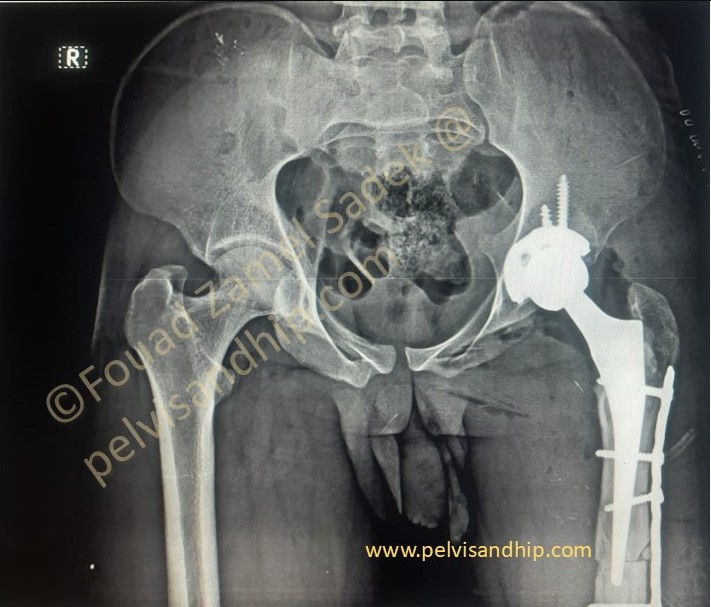

The final picture with the completed reconstruction provided a well aligned stable construct with a balanced pelvis and corrected leg length.

Fixation of the osteotomy carefully carried out did not jeopardise a good cementing technique an essential part to ensure longevity

At 3 months follow up. Patient is walking full weight bearing with no support. The amount of union at the osteotomy site is quite reassuring.